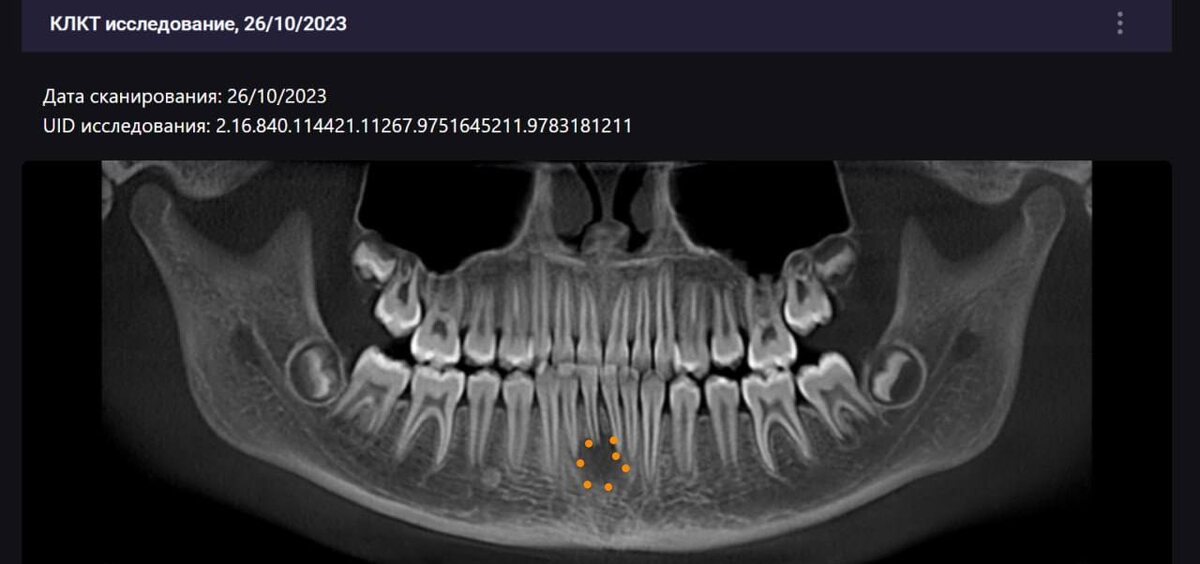

Кейс с травмой 41-го зуба в динамике

Коллеги, поделюсь своим кейсом, хочу показать его в динамике. Пациент - девочка, пришла на прием с апикальным периодонтитом в обострении. У ребенка — температура, отёк, три дня не спала, и всё это из-за 41 зуба. ❗️Важно - травма была за год до приёма. Тогда зуб был целый, девочка просто немного ударилась подбородком. Через год — сильная боль, обострение. Дальше по этапам: — сначала приём антибиотиков, — затем лечение корневых каналов, — и уже в динамике (май 2025) мы видим положительный результат. Как понимаем, что динамика положительная? Очаг поражения уменьшается, идёт этап заживления костной ткани. Продолжаем наблюдать пациента дальше.